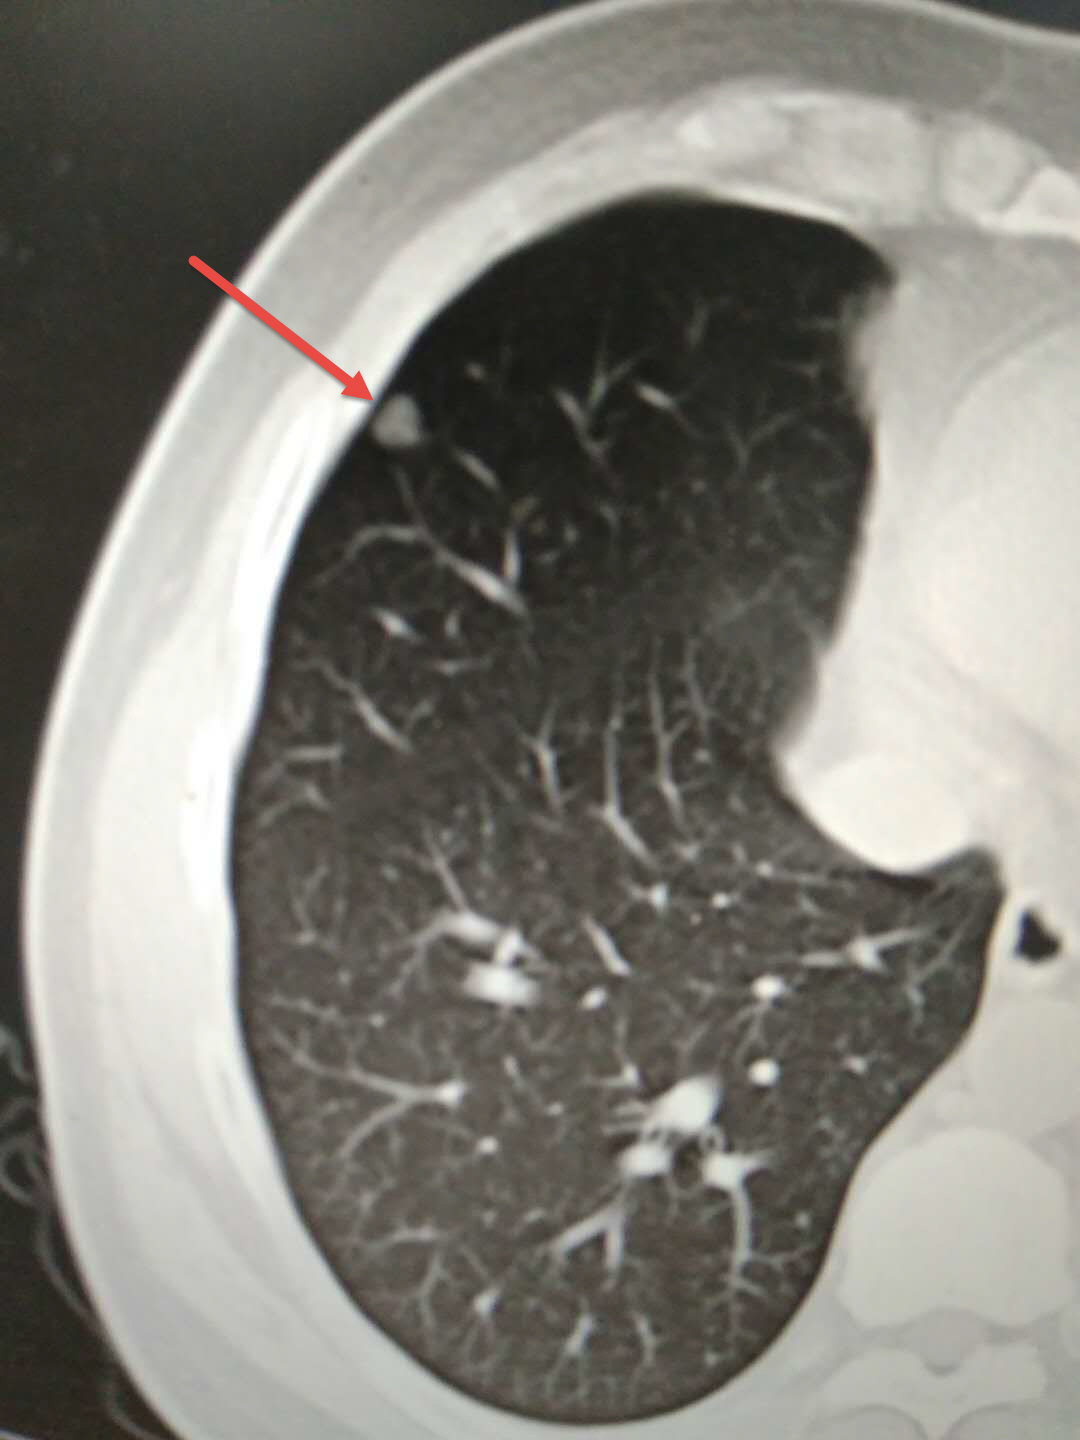

这是一位40岁的男性,发现肺磨玻璃结节3年,结节从5mm逐渐长大至7mm。

我们给予穿刺针活检,穿刺病理为不典型腺瘤样增生增生(AAH),给予射频消融治疗。定位15min,手术15min,一共30min结束。术中术后无出血和气胸。观察一晚后,第二天出院。

术后同时给予线粒体能量治疗,随访2年,肺结节消失,残留纤维条索影。

这是一例常规的射频消融治疗肺结节(不典型腺瘤样增生,AAH)的病例。整个治疗经过体现了,随访、穿刺、诊断、射频局部治疗,线粒体系统全身治疗的整体治疗理念。可以为肺结节患者的诊治提供很好的借鉴经验。